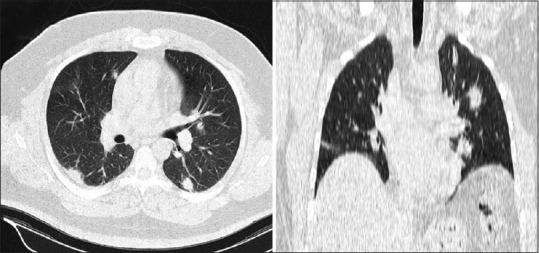

The Radiologic Society of North America (RSNA) divides patients into four sections: negative, atypical, indeterminate, and typical coronavirus disease 2019 (COVID-19) pneumonia based on their computed tomography (CT) scan findings. Herein, we evaluate the frequency of the chest CT-scan appearances of COVID-19 according to each RSNA categorical group.

According to the RSNA classification 87.8, 5.56, 4.44, and 2.22% of the patients were assigned as typical, indeterminate, atypical, and negative, respectively. The proportion of "atypical" patients was higher in the patients who had mediastinal lymphadenopathy and pleural effusion. Moreover, ground-glass opacity (GGO) and consolidation were more pronounced in the lower lobes and left lung compared to the upper lobes and right lung, respectively. While small nodules were mostly seen in the atypical group, small GGO was associated with the typical group, especially when it is present in the right lung and indeterminate group.

Regardless of its location, non-round GGO is the most prevalent finding in the typical group of the RSNA classification systems. Mediastinal lymphadenopathy, pleural effusion, and small nodules are mostly observed in the atypical group and small GGO in the right lung is mostly seen in the typical group.